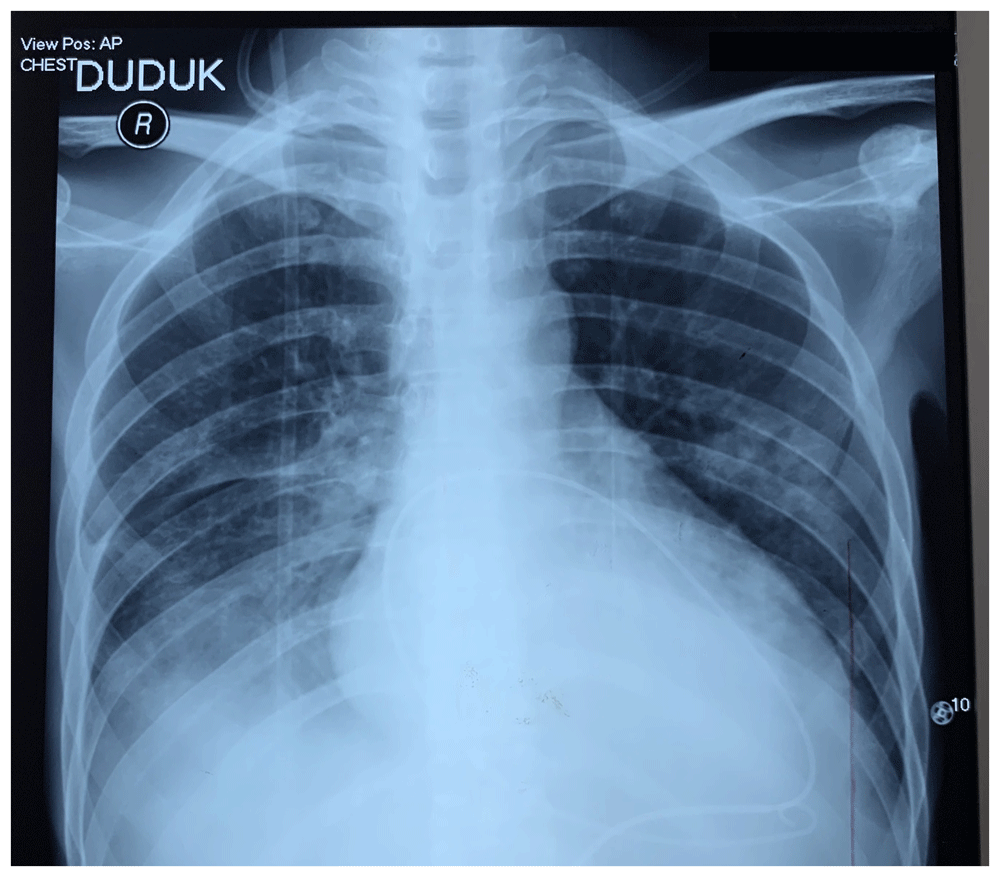

A temporary pacemaker was immediately implanted as the patient showed symptomatic heart block and cardiogenic shock. CHB persisted despite corrected electrolyte imbalance. On the 14th day of admission, the patient developed pleural effusion, and worsening pericardial effusion with echocardiogram showed massive pericardial effusion and sign of tamponade. Further chest X-ray evaluation on the 14th day of treatment (which includes electrolyte imbalance correction, supportive treatment of general weakness condition, anemia, hypoalbuminemia, and infection) showed left parahilar ground glass appearance with suspicions of lung metastasis and pleural effusion (Figure 4). Pericardiocentesis was then performed with pericardial fluid showing hemorrhagic typical for malignant disease.

Pericardial fluid pigtail was already inserted for drainage of pericardial effusion.